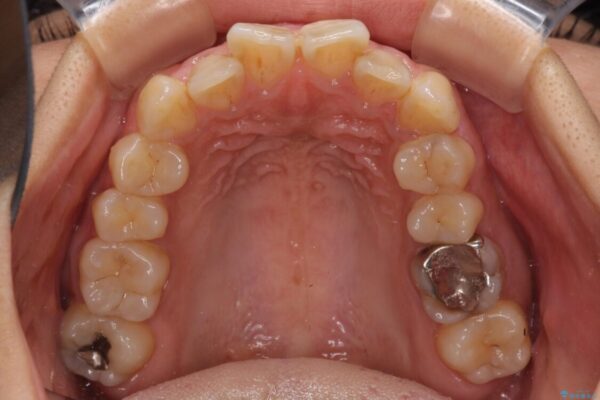

前歯のデコボコと上顎の前突感による口の閉じにくさを気にして来院された患者様です。

治療前

• デコボコと口元の突出感 ハーフリンガルでの抜歯矯正 治療前画像